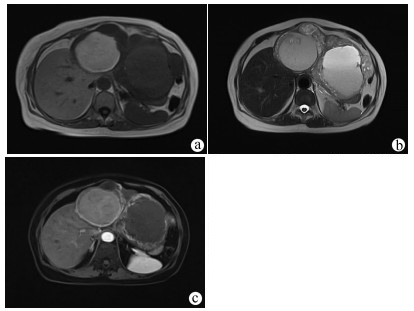

Application of transjugular liver biopsy in the diagnosis and treatment of complicated and severe liver diseases

Hua TIAN, Qiang YU, Shaoli YOU, Sa LYU, Shuhong LIU, Bing ZHU

2021, 37(12): 2874-2877. DOI: 10.3969/j.issn.1001-5256.2021.12.027

Abstract(1173) HTML (235) PDF (2586KB)(79)

Abstract:

Objective  To investigate the application value of transjugular liver biopsy (TJLB) in the diagnosis and treatment of complicated and severe liver diseases.  Methods  A retrospective analysis was performed for the clinical data of 31 patients who underwent TJLB in The Fifth Medical Center of Chinese PLA General Hospital, including indication for puncture, success rate, and final diagnosis.  Results  Among the 31 patients, there were 15 male patients and 16 female patients. Percutaneous liver biopsy was unsuitable for 8 patients with liver failure and disturbances of blood coagulation, 13 with liver cirrhosis and ascites, and 10 with liver cirrhosis and thrombocytopenia (< 50×109/L), which were the indications for TJLB. The success rate of TJLB puncture was 100%, with 2-4 passes for puncture. No serious adverse event was observed. Of all 31 patients, 26 (83.87%) had a definite diagnosis at discharge, among whom there were 5 patients with idiopathic portal hypertension, 9 patients with drug-induced liver failure or liver cirrhosis, 5 patients with autoimmune liver disease, and 7 patients with liver cirrhosis or liver failure due to other causes, and 5 patients had unknown etiology. In addition, 3 patients underwent biopsy to confirm the diagnosis and decision of whether liver transplantation should be performed.  Conclusion  TJLB plays an important role in the diagnosis and treatment of complicated and severe liver diseases and still has certain limitations, and therefore, suitable patients should be selected in clinical practice.